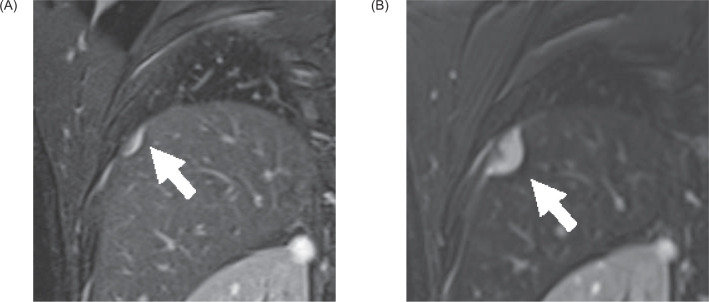

我们报告了一名 38 岁男性的病例,他患有两个与冯-希佩尔-林道病相关的 T1a 肾细胞癌(RCC)(见图 1)。

We report the case of a 38-year-old man with two von Hippel-Lindau disease-associated T1a renal cell carcinomas (RCCs) (<2 cm in diameter) which developed into a 2.5-cm solitary diaphragmatic metastatic tumor. After diagnosis using percutaneous biopsy, the diaphragmatic metastasis and two RCCs were treated by laparoscopic resection and percutaneous cryoablation, respectively. One year after treatment, the patient survived without local recurrence or distant metastasis. This report describes a rare case of RCC metastasis in VHL disease and its treatment.